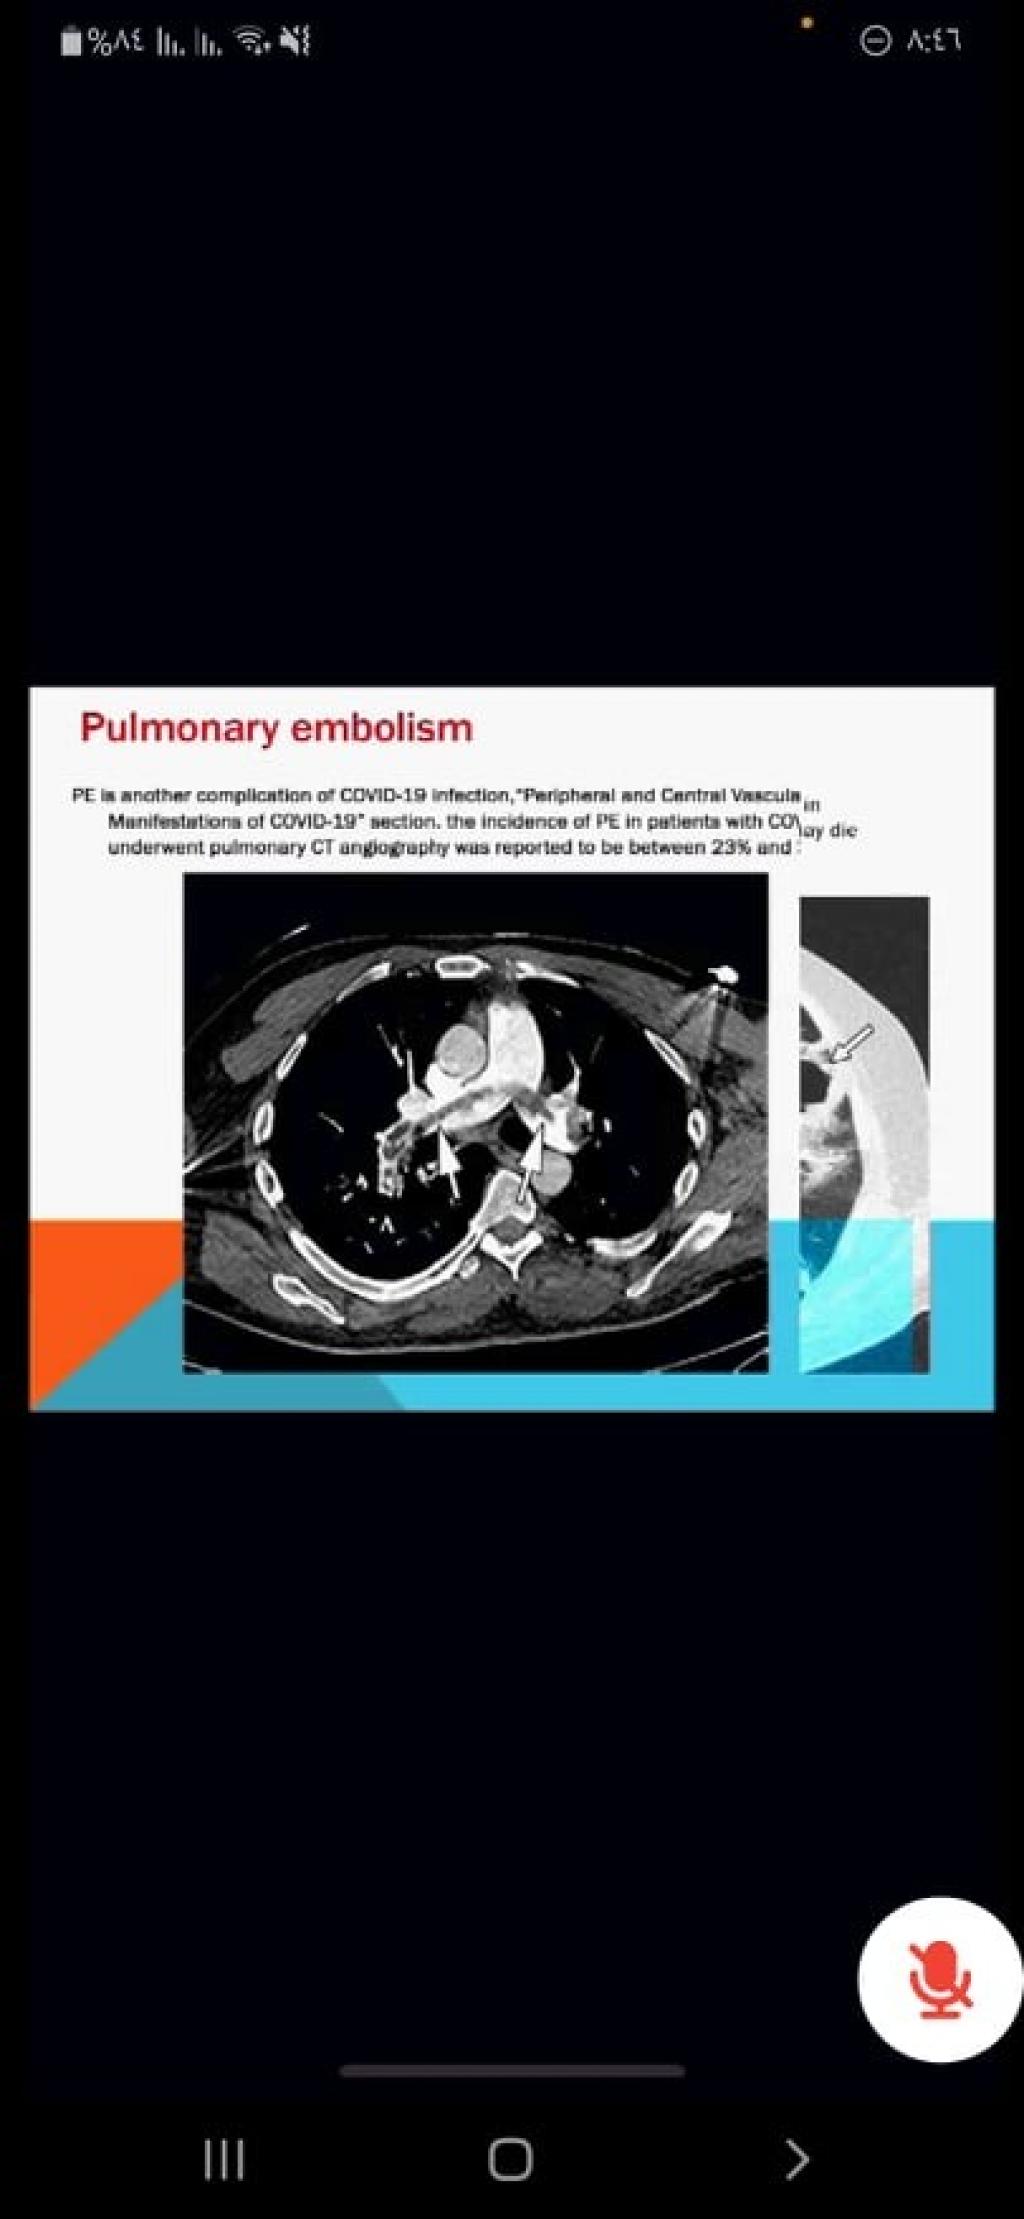

اقام فرع الاشعة كلية الطب جامعة الموصل ندوته العلمية السنوية الموسومة (السمات الشعاعية لمرض كوفيد -19 في الفحوصات الشعاعية والأمواج فوق الصوتية والمفراس والرنين) ، عقدت الندوة افتراضياً مساء الخميس 25 شباط 2021، برعاية رئيس الجامعة الأستاذ الدكتور قصي كمال الدين الاحمدي، وبإشراف وحضور عميد الكلية الأستاذ الدكتور باسل محمد نذير سعيد وعدد من التدريسيين والأكاديميين والباحثين من داخل الجامعة وخارجها.

هدفت الندوة الى توعية الاطباء بصورة عامة واطباء الاشعة بصفة خاصة بالسمات الشعاعية للمرض باستخدام انماط التصوير الطبي المختلفة.

توصلت الندوة إلى امكانية استخدام انماط التصوير المختلفة كالأشعة والسونار والمفراس والرنين في التشخيص الطبي لمرض كوفيد-19.